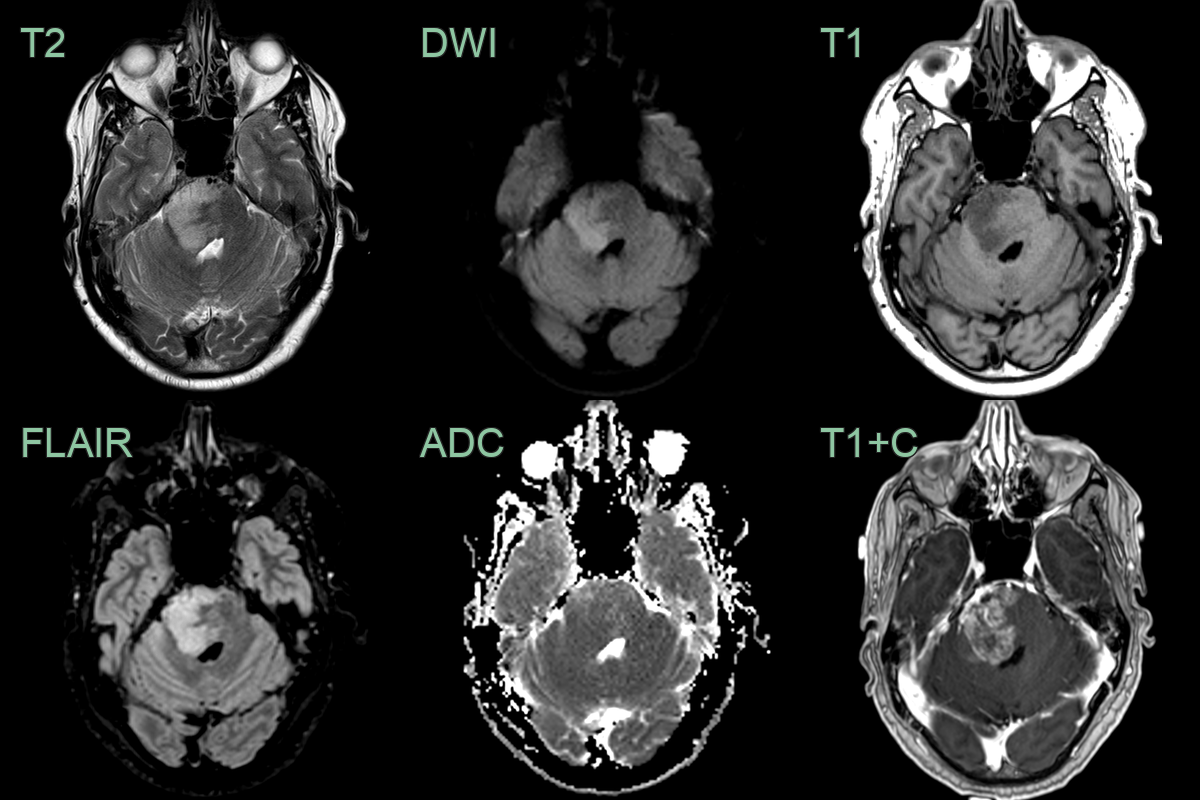

- A 55-year-old patient presented with headache, nausea and vomitting.

- MRI showed an enhancing lesion in the right side of the pons with slightly reduced ADC values.

- Given an extensive travel history the imaging differential included both neoplasta and infection/inflammation.

- Biopsy revealed an H3 27M-mutant diffuse midline glioma.